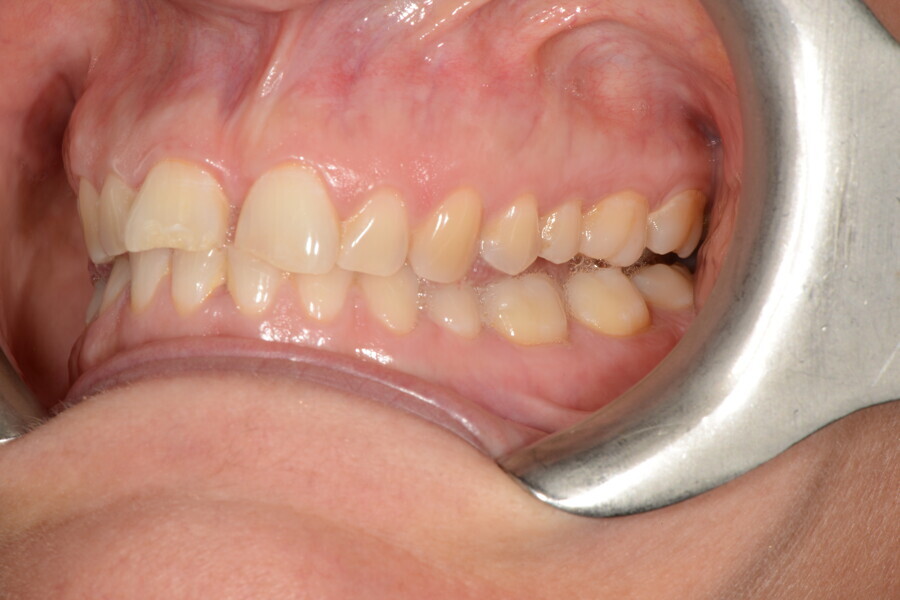

The 58-year-old patient wished to improve his oral aesthetics and function, complaining of mobility of the posterior teeth and wear of the anterior teeth. After data collection, a very complex situation was identified (Figs. 11–13):

1. severe periodontitis with poor prognosis of some teeth;

2. anterior crossbite;

3. severe wear mainly of the anterior teeth and compensatory eruption;38

4. atypical swallowing and lower posture of the tongue at rest;

5. masticatory dysfunction during the mastication test; and

6. no significant signs of temporomandibular disorder.

After the first phase of aligner treatment, we had achieved better inter-arch coherence, better maxillary arch expansion, and some space for improving the anterior tooth proportions restoratively (Fig. 19). We then temporarily restored the anterior teeth directly with composite, closing the spaces, improving the tooth proportions and further increasing the maxillary arch expansion (Fig. 20). We used restorative arch expansion to reduce the orthodontic destabilisation of the teeth to achieve the correct inter-arch coherence and retain the teeth in the cortical bone.38 A refinement aligner phase was undertaken to improve the final alignment of the gingival zenith and to improve the inter-arch coherence (Fig. 21). The periods of the first orthodontic phase and of the refinement were used to augment the mandibular and maxillary bone and to place the implants (Fig. 22). At the end of the orthodontic treatment, the case was finalised with ceramic veneers in the anterior area and temporary restorations on the implants in the posterior area (Figs. 23–26).